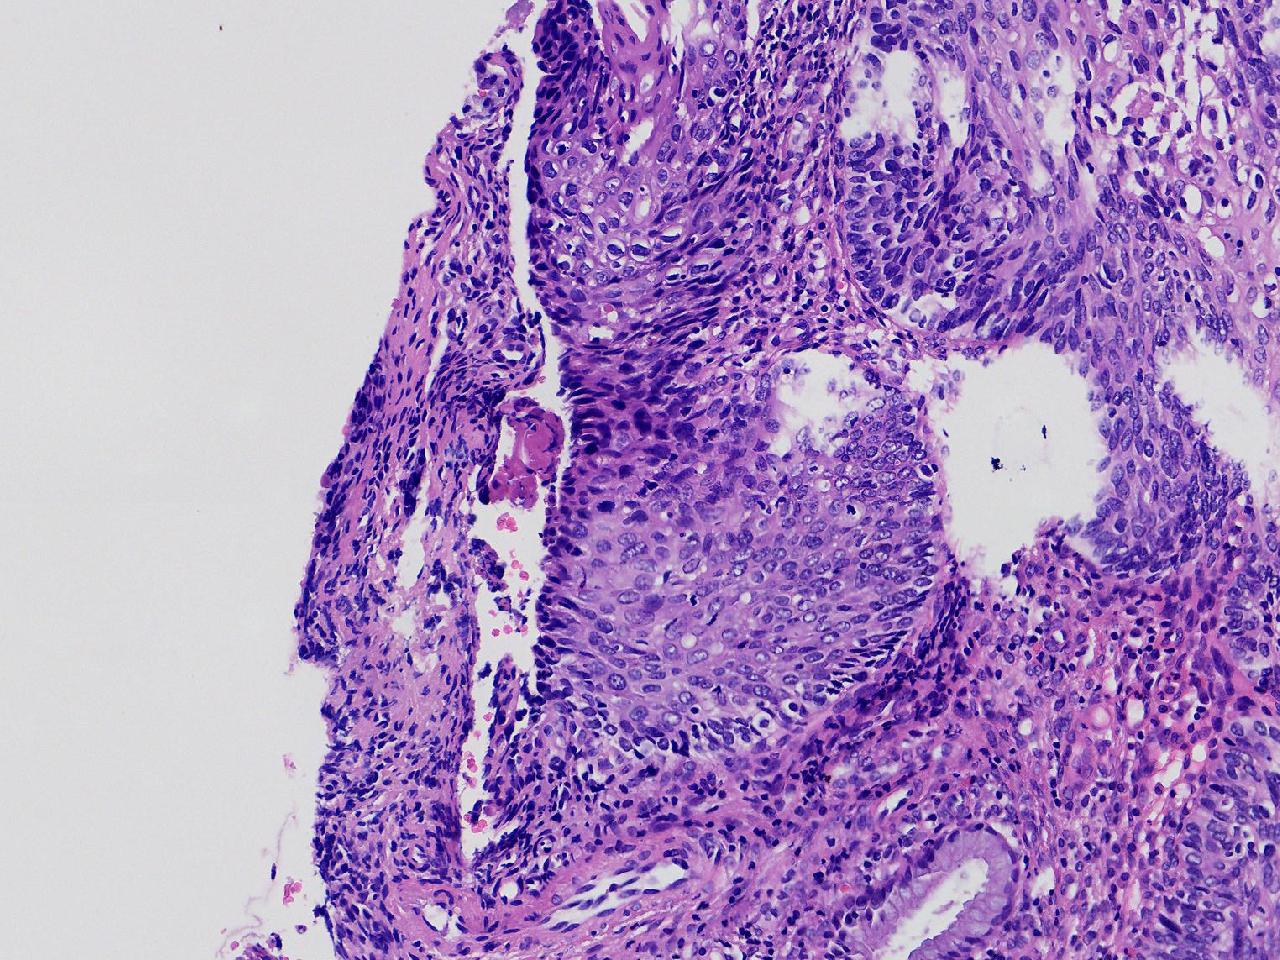

CIN1级? CIN2级?

女,49岁,宫颈11点活检,HPV:16+ 42+

宫颈11点活检。

灰白色不整形软组织1块。

图2

2级

2级,累腺。